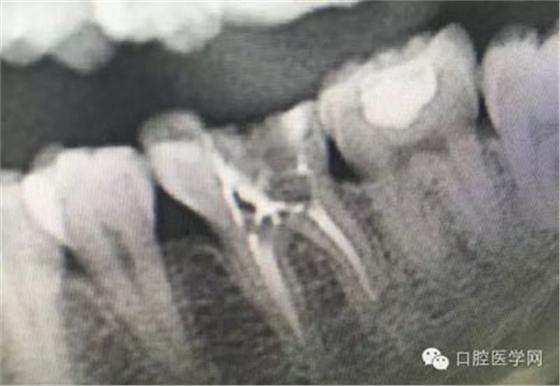

這是一例外院樹脂修復(fù)后十個(gè)月出現(xiàn)牙髓炎癥狀的患者。遇到這樣子的患者大家會(huì)怎么做,證明選擇,還有就是可做可不做治療的如何去平衡。

根管治療,我們?cè)诖髮W(xué)的時(shí)候就學(xué)習(xí)的東西,標(biāo)準(zhǔn)就在那里放著,可是很多時(shí)候我們熟視無(wú)睹,放任我們的想象去做。我們多些重視,多些心思,會(huì)好很多,認(rèn)真對(duì)待每顆牙齒。